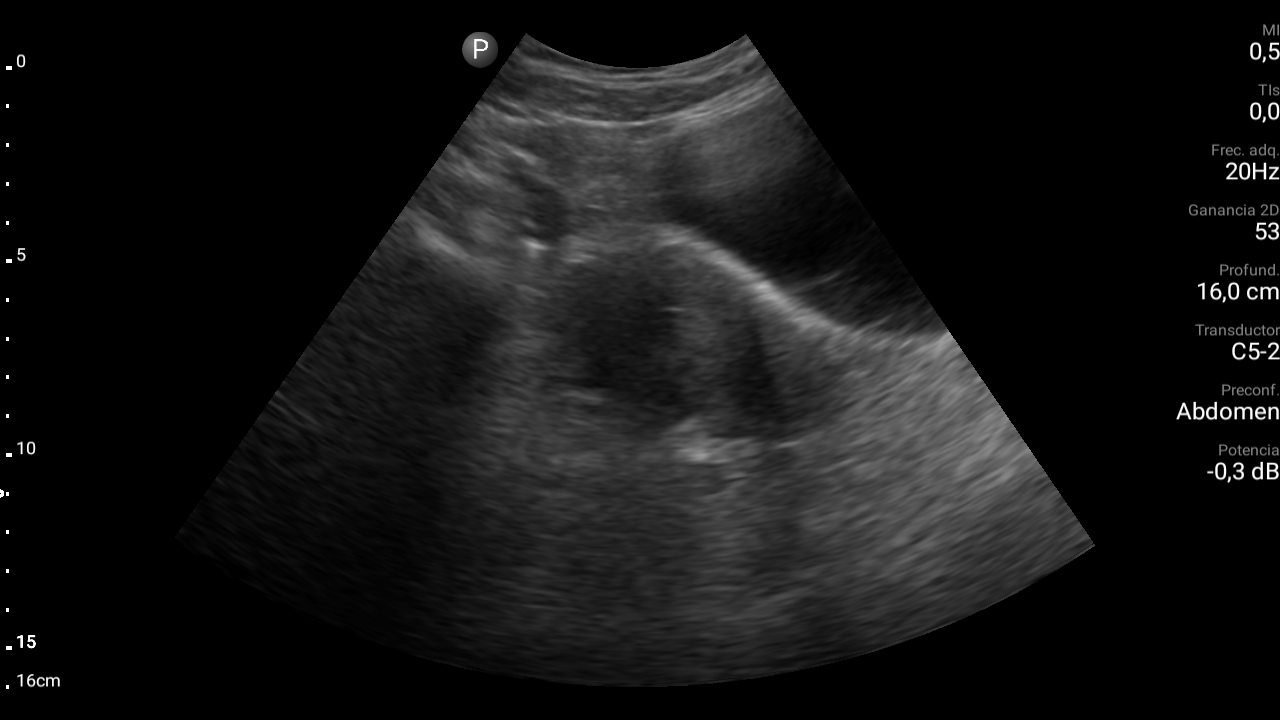

Ecografía abdominal: se observa masa hipoecoica dependiente de útero por lo que se remite de forma preferente a ginecología.